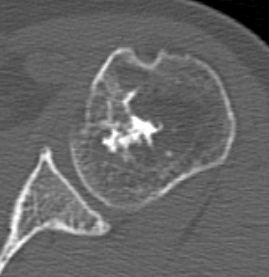

CT Scan

Endosteal scalloping

Large, central enchondroma